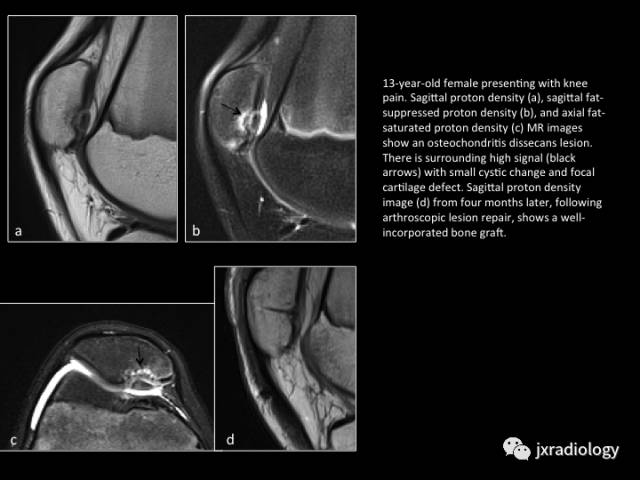

Fig. 14: Unstable osteochondritis dissecans lesion

图14:不稳定的剥脱性骨软骨炎

13岁女孩膝关节疼痛;a,b,c图示髌骨局部骨软骨病灶周围见液体信号影;d图关节镜修复后4个月复查,显示移植骨愈合良好。